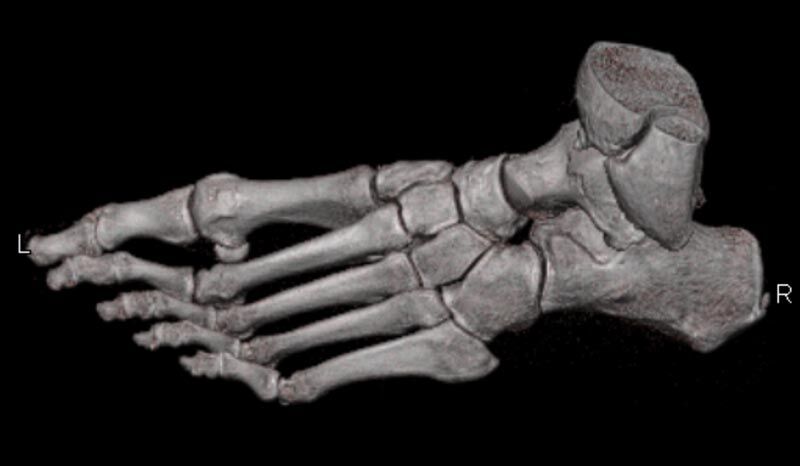

Extremitäten

• bei komplizierten Frakturen z. B. in der Nähe von Gelenken oder im Bereich der Handwurzel und Fußwurzel

Spezielle Software ermöglicht jetzt zum Beispiel:

• verbesserte Bildqualität bei Patienten mit Implantaten (z. Bsp. Hüftendoprothesen)

• besonders hochauflösende, strahlendosissparende Darstellung aller Skelettstrukturen